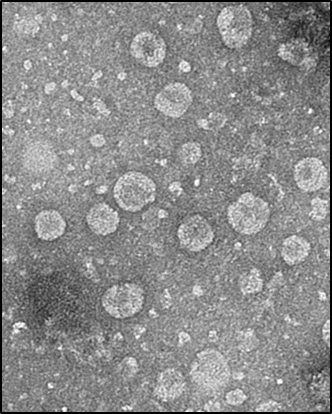

엑소솜(exosome, 세포외 소포체)은 생명체가 세포 간 정보 전달을 위해 분비하는 진화적으로 보존된 100 나노미터(nm) 내외 크기의 천연 나노물질이다. 또 생체 친화적으로 효능 물질을 다른 생명체나 세포에 빠르게 정확하게 전달할 수 있어, 최근 전 세계 생명과학 및 의학 분야에서 주목하고 있다.